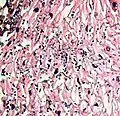

A severe case of candidiasis